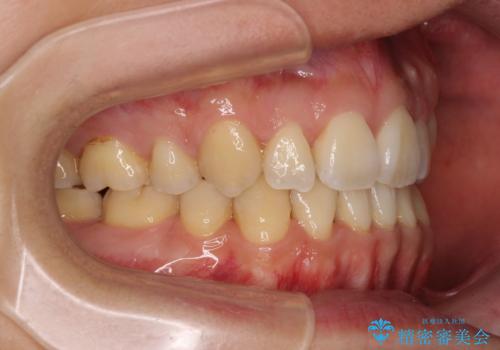

重なり合って磨きにくい前歯 ワイヤー装置での抜歯矯正

- 前歯の著しいデコボコを気にして来院された患者様です。

上顎の左右側切歯(前から2番目)が裏側に隠れいてる状態で、咬み合わせや清掃性に大きな問題が認められました。

元の歯列が想像できないほど、きれいな歯列に整えることができました。

第二小臼歯抜歯の矯正治療は、治療期間が長引くことが多いですが、動きが非常に良く、予定の治療期間で終えることができました。